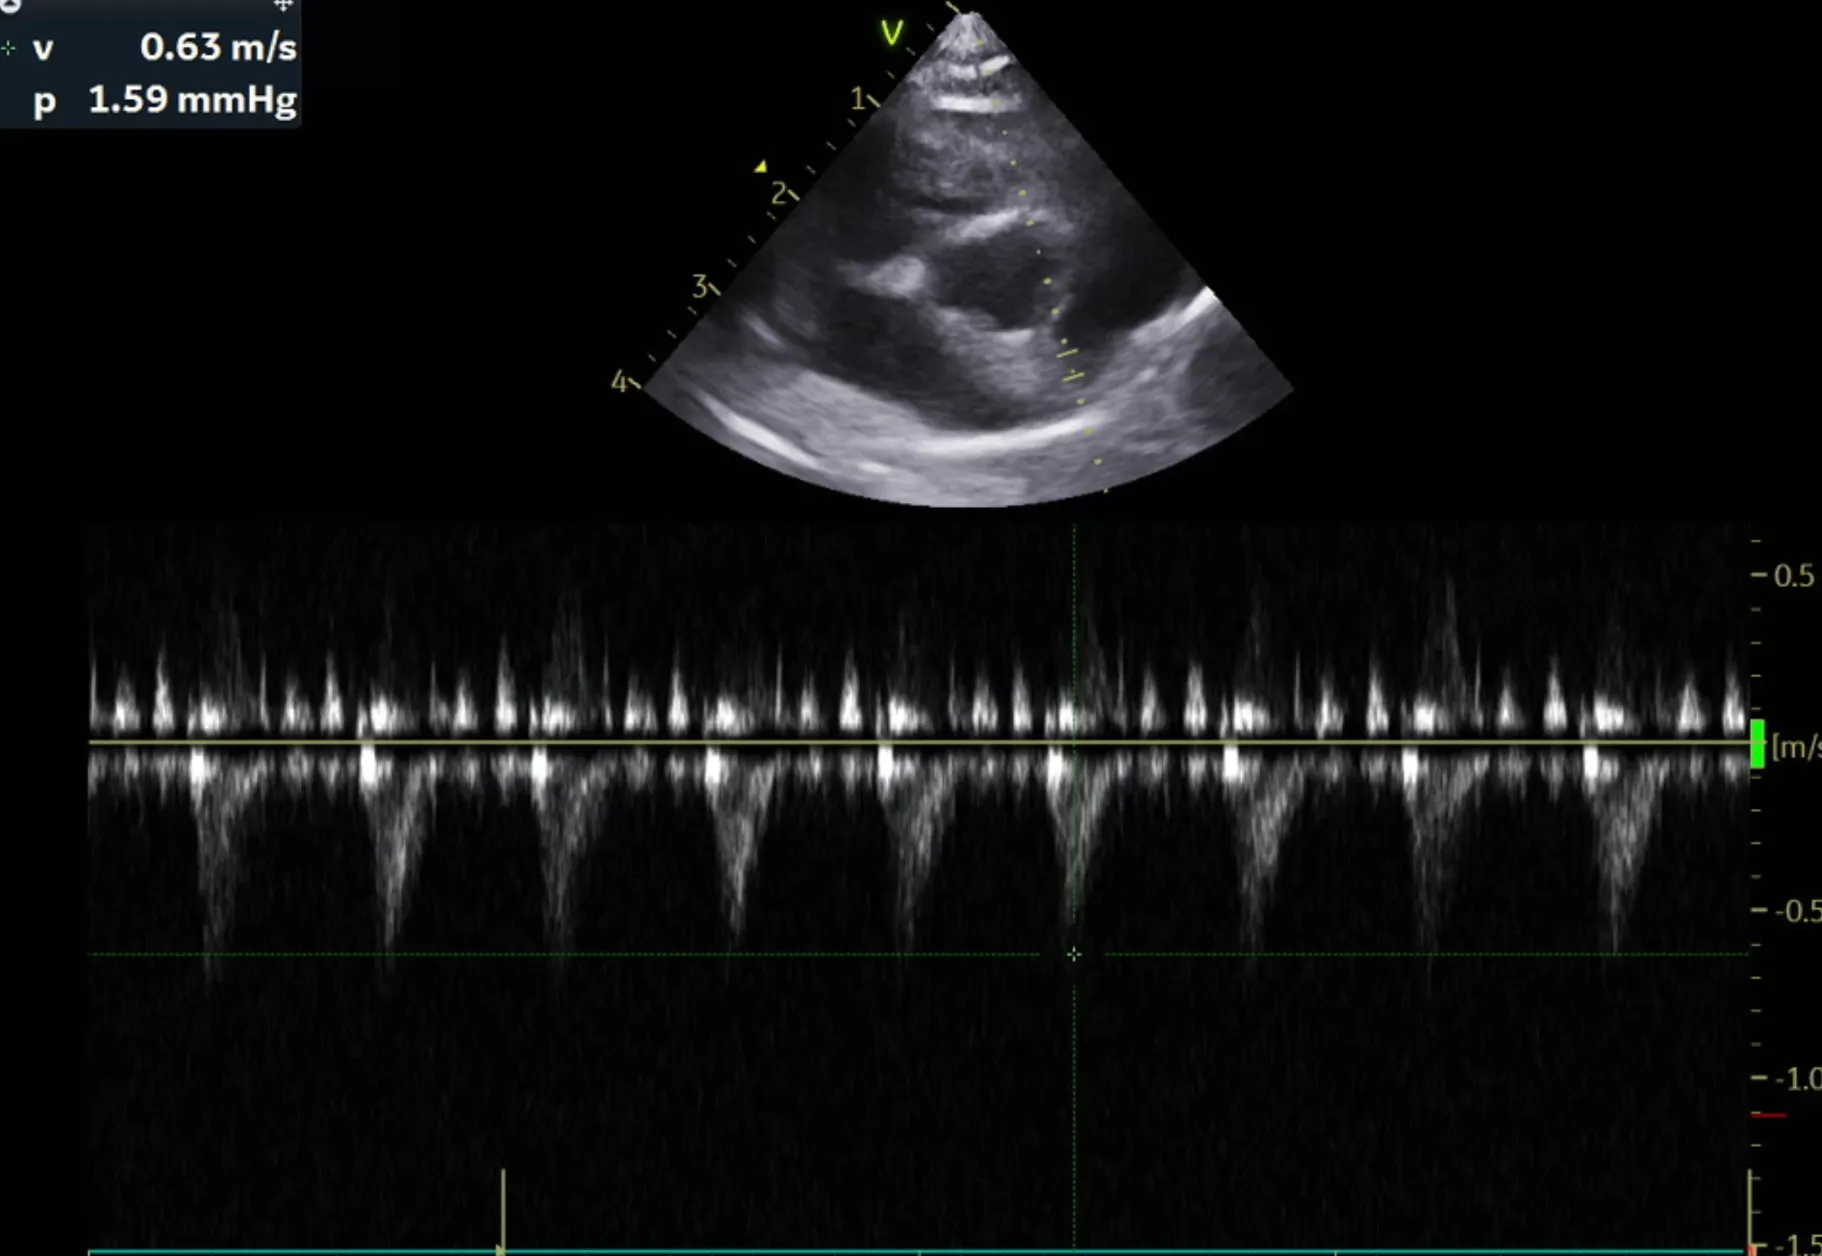

2. 심장 초음파 검사 결과

곰이 의 심장초음파 영상전공의 소견은 다음과 같습니다.

RPS long axis 4 chamber view

LA와 RA내 aliasing pattern 관찰안됨.

LA dilation 관찰안됨.

RPS short axis heart base view

LA/Ao ratio 1.47로 정상범위(0.88-1.7), 유의미한 LA 확장 없음

Left apical 4 chamber view

유의미한 MR flow, TR flow 관찰되지 않음

주치의 소견은 다음과 같습니다.

곰이 는 심장 초음파 검사 결과 현재 심잠벽의 두께는 정상이며 수축기능, 이완기능(심장이 정상적으로 잘 뛰는 것을 확인하는 검사) 모두 정상입니다.

심장 초음파는 1년에 한번씩 검사 받는 것을 추천드립니다.